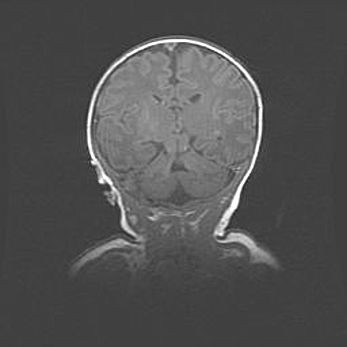

Наружная гидроцефалия с возможной атрофией височных областей.

Возраст: 28 дней

Вес: 3670 г

Пол: мужской

Окружность головы: 38 см

Срок гестации: 40 недель

Гидроцефалия головного мозга у новорожденных – это заболевание, которое характеризуется скоплением избыточного количества спинномозговой жидкости в желудочковой системе головного мозга в результате затруднения её перемещения от места выработки к месту поглощения в кровеносную систему или вследствие нарушения абсорбции. При открытой наружной форме гидроцефалии у новорожденных расширяются и переполняются субарахноидные пространства.

При нормотензивных  формах,  которые,  как  правило,  являются  следствием  перенесенных ишемических  повреждений  паренхимы  мозга,  возможно  сочетание микроцефалии  с нормотензивной гидроцефалией. В основе данных изменений лежит атрофия больших полушарий с преимущественной  локализацией  в  лобно-височных  областях.